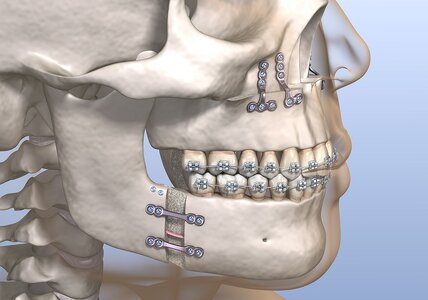

I’m 22 years old self-made multimillionaire with LTN-MTN face white guy with brown eyes brown hair. These are the surgeries that I need. 174cm, narrow frame (whatever). The face surgeries have the chance to shoot me into HTN territory.

3 years of pain, hundreds of thousands of dollars, and years spent living in geo-minned locations near world renowned doctors in Europe… face surgeries is about 1.5 years.

I’m 22 years old self-made multimillionaire with LTN-MTN face white guy with brown eyes brown hair. These are the surgeries that I need. 174cm, narrow frame (whatever). The face surgeries have the chance to shoot me into HTN territory.

3 years of pain, hundreds of thousands of dollars, and years spent living in geo-minned locations near world renowned doctors in Europe… face surgeries is about 1.5 years.